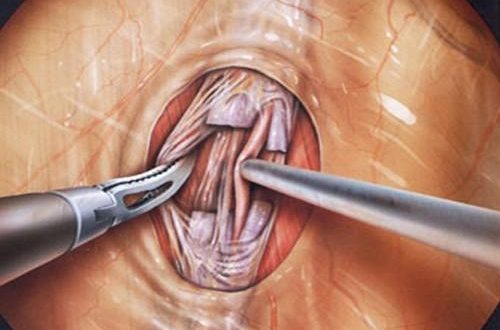

درمان واریکوسل با جراحی لاپاروسکوپ

عملیات بالا همچنین می تواند به صورت یک روش لاپاروسکوپی (از طریق برش های کوچک با یک دوربین) و از طریق سه برش کوچک در شکم برای عبور لولهها انجام شود. جراحی لاپاروسکوپی از طریق لولههای نازک که از طریق یک برش کوچک به بدن وارد میشود، انجام میگردد. ابتدا درون بدن با گاز برای دید بهتر پر شده و سپس جراح از یک دوربین مخصوص قرار گرفته انتهای لوله دستگاه برای دیدن داخل بدن استفاده میکند. جراحی لاپاروسکوپی نیز تحت بیهوشی عمومی انجام میشود.